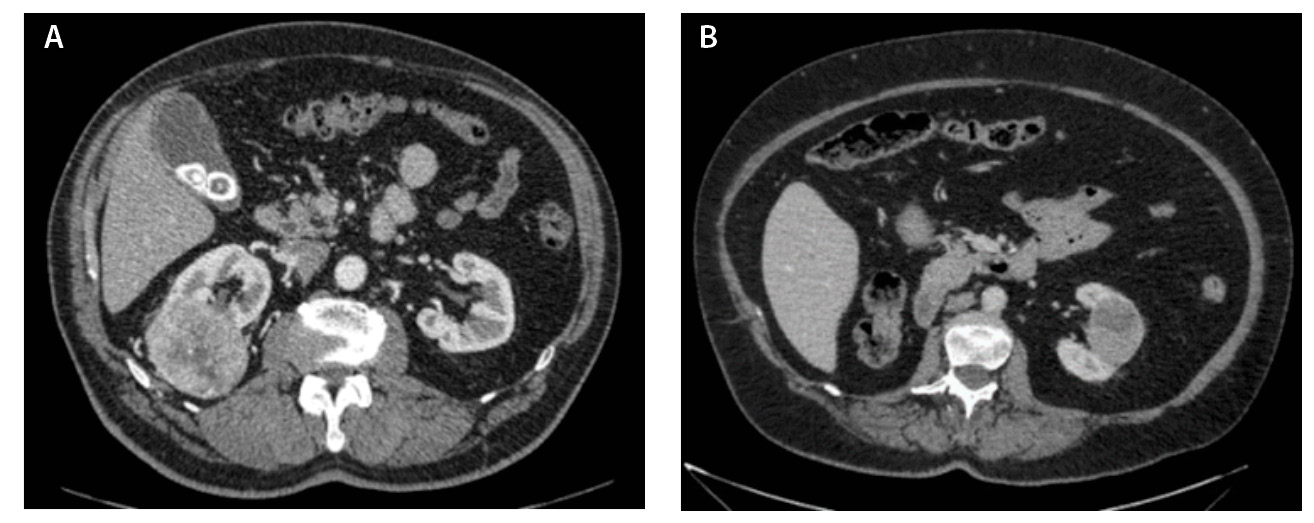

Компьютерная томография (КТ) с внутривенным контрастным усилением широко используется как метод диагностики и первичного стадирования скПКР. В настоящее время наиболее значимыми характеристиками опухоли для предоперационного стадирования и планирования хирургического лечения скПКР признаны расположение, размер опухоли и признаки ее инвазивного роста [3–6], а структура и характер контрастирования позволяют дифференцировать типы ПКР, но ни один из этих показателей не дает возможности достоверно прогнозировать степень дифференцировки опухоли. Структура скПКР любой степени дифференцировки, как правило, гетерогенная с наличием солидного и кистозного компонентов. Признаки инвазивного роста опухоли, наличие метастазов позволяют предположить низкую степень дифференцировки опухоли, однако не являются достоверными признаками. Как видно на рис. 1, скПКР разной степени дифференцировки по данным КТ выглядят практически идентично: в обоих случаях визуализируется опухолевый тромб в почечной вене с распространением в просвет нижней полой вены. Такие характеристики, как размер опухоли, пофазное накопление контрастного вещества и градиент накопления контрастного вещества при КТ-исследовании, также не являются строго специфичными для разных степеней дифференцировки скПКР (рис. 2).

Рис. 2. Светлоклеточный почечно-клеточный рак. А – Grade 1 (данные компьютерной томографии пациента С.), кортико-медуллярная фаза исследования: трансмуральная опухоль правой почки размером 6,6 см, с четкими и ровными контурами, прилежит к синусу почки, опухоль имеет солидно-кистозное строение, солидный компонент опухоли накапливает контрастное вещество (КВ) менее интенсивно, чем кортикальный слой почки, градиент накопления КВ солидным компонентом опухоли 50–60 HU. Б – Grade 4 (данные компьютерной томографии пациентки Щ.), кортико-медуллярная фаза исследования: трансмуральная опухоль левой почки размером 5,2 см, с четкими и ровными контурами, прилежит к синусу почки, опухоль имеет солидно-кистозное строение, солидный компонент опухоли накапливает КВ менее интенсивно, чем кортикальный слой почки, градиент накопления КВ солидным компонентом опухоли 45–60 HU